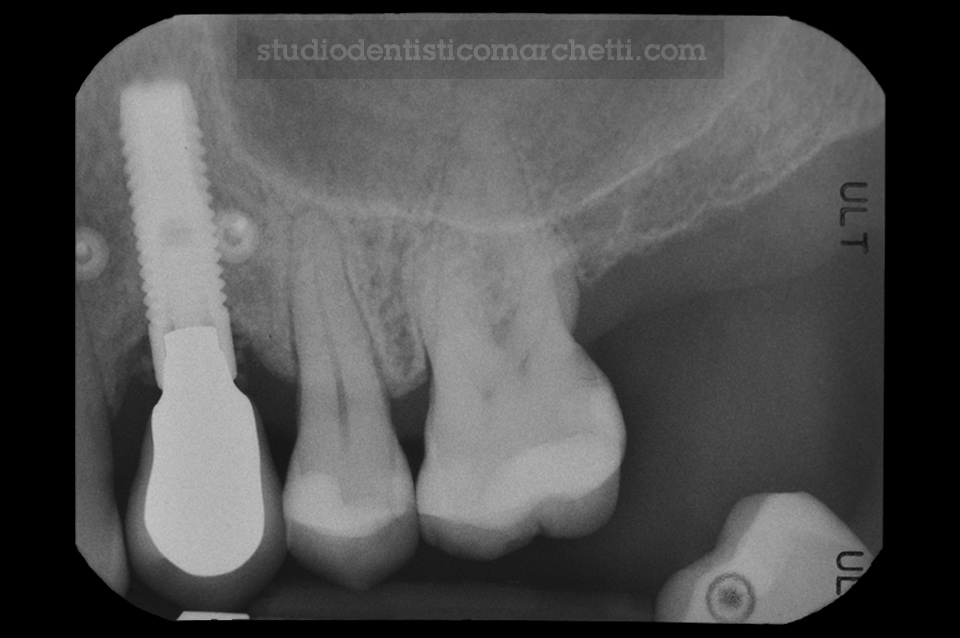

Implantologia e Trattamento delle Preimplantiti

Trattamento della Perimplantite

Implantologia e Trattamento delle Preimplantiti / Odontoiatria Protesica

Protesi Fissa su Dente Naturale e su Impianti